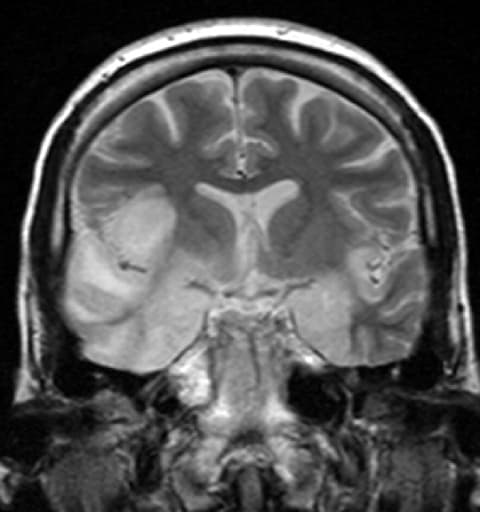

Encephalitis is inflammation of the brain. The severity can be variable with symptoms including reduction or alteration in consciousness, headache, fever, confusion, a stiff neck, and vomiting. Complications may include seizures, hallucinations, trouble speaking, memory problems, and problems with hearing. Causes of encephalitis include viruses such as herpes simplex virus and rabies virus as well as bacteria, fungi, or parasites. Other causes include autoimmune diseases and certain medications. In many cases the cause remains unknown. Risk factors include a weak immune system. Diagnosis is typically based on symptoms and supported by blood tests, medical imaging, and analysis of cerebrospinal fluid. Certain types are preventable with vaccines. Treatment may include antiviral medications (such as acyclovir), anticonvulsants, and corticosteroids. Treatment generally takes place in hospital. Some people require artificial respiration. Once the immediate problem is under control, rehabilitation may be required. In 2015, encephalitis was estimated to have affected 4.3 million people and resulted in 150,000 deaths worldwide. Adults with encephalitis present with acute onset of fever, headache, confusion, and sometimes seizures. Younger children or infants may present with irritability, poor appetite and fever. Neurological examinations usually reveal a drowsy or confused person. Stiff neck, due to the irritation of the meninges covering the brain, indicates that the patient has either meningitis or meningoencephalitis. Viral encephalitis and Herpesviral encephalitis Viral encephalitis can occur either as a direct effect of an acute infection, or as one of the sequelae of a latent infection. The majority of viral cases of encephalitis have an unknown cause, however the most common identifiable cause of viral encephalitis is from herpes simplex infection. Other causes of acute viral encephalitis are rabies virus, poliovirus, and measles virus. Additional possible viral causes are arboviral flavivirus (St.